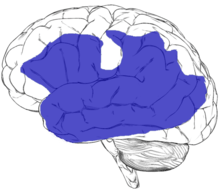

Substantial damage to tissue anywhere within the region shown in blue on the figure below can potentially result in aphasia.[19] Aphasia can also sometimes be caused by damage to subcortical structures deep within the left hemisphere, including the thalamus, the internal and external capsules, and the caudate nucleus of the basal ganglia.[20][21] The area and extent of brain damage or atrophy will determine the type of aphasia and its symptoms.[2][17] A very small number of people can experience aphasia after damage to the right hemisphere only. It has been suggested that these individuals may have had an unusual brain organization prior to their illness or injury, with perhaps greater overall reliance on the right hemisphere for language skills than in the general population.[22][23]